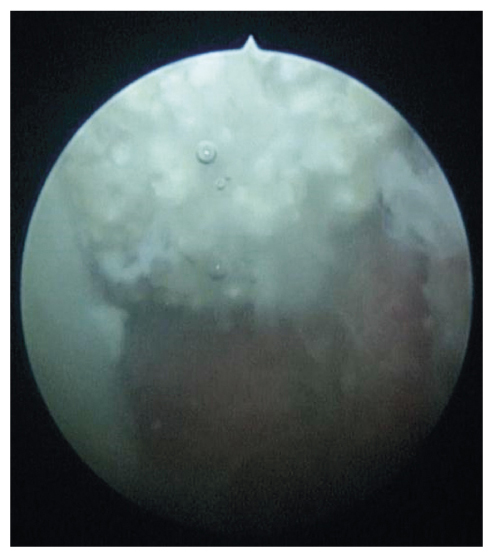

Пациенту выполнена цистоуретроскопия, на которой слизистая шейки, пришеечного отдела и тела пузыря гиперемирована, отёчна, значительно утолщена, с папилломатозными разрастаниями. В полости мочевого пузыря визуализировались множественные наложения фибрина (см. рис. 2).

Рис. 2. Цистоуретроскопия: слизистая стенки мочевого пузыря пациента с наложениями фибрина.

Fig. 2. Cystourethroscopy: mucosa of the patient’s bladder wall with fibrin deposits.